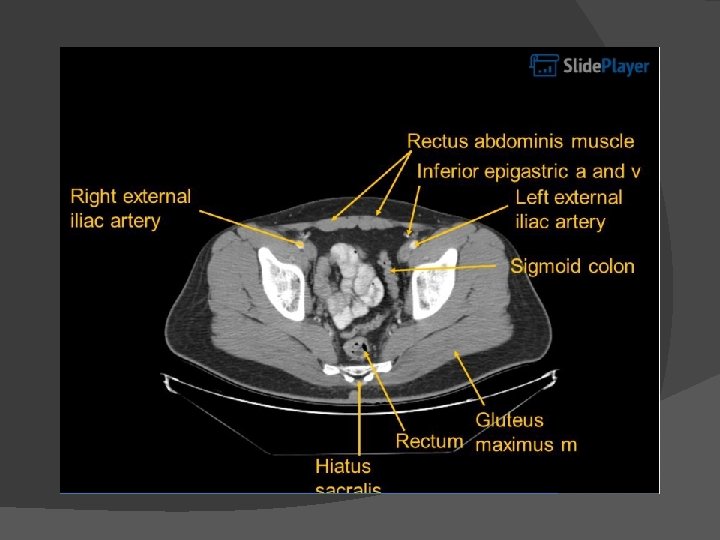

Abdominal CT